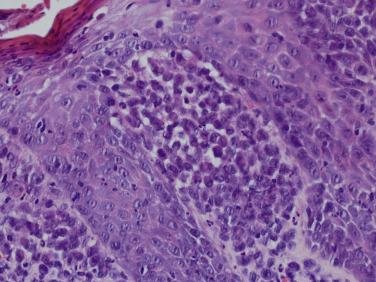

In the skin, an infiltrate of LCH cells is most often observed in the papillary dermis ( Fig. 22-3 ), but can also present in a nodular fashion in the dermis or in a perifollicular distribution. The epidermis is also typically infiltrated by LCH cells, sometimes giving a pagetoid appearance. LCH cells are large, and often have a reniform-shaped nucleus with abundant eosinophilic cytoplasm. The infiltrate commonly occurs along with eosinophils (sometimes numerous) and lymphocytes, and sometimes scattered plasma cells, mast cells, and neutrophils. Giant cells can occasionally be observed. LCH cells are confirmed by their expression of CD1a, S100, and Langerin (CD207), and their typical lack of expression for CD68, CD163, and factor XIIIa.